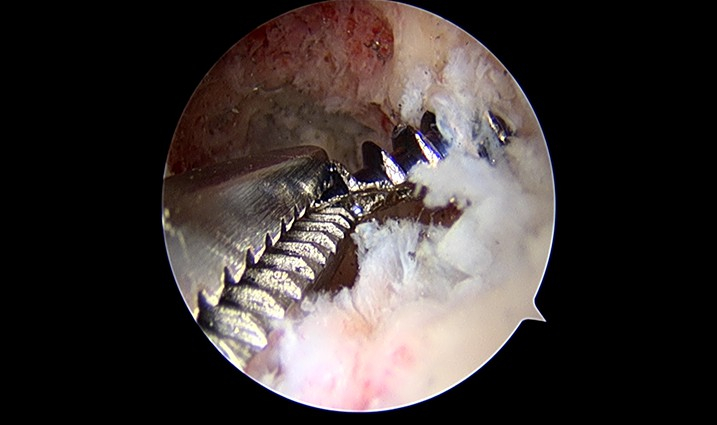

輔大骨科全方位內視鏡治療包括肩、膝、肘、腕、踝、髖等關節鏡及脊髓腔鏡等,傷口較少,醫師使用先進的器械,治療更細微的病灶,看得更深入,治療得更廣泛,更精準治療病灶。葉炳君說:「有時候連紅血球在流動都看得到。」他分享三個案例,應用肩關節鏡旋轉肌腱修補手術的病人第二天就可以出院,肘關節鏡手術的病人四個星期手肘活動由10-100度恢復到0-130度,經皮脊椎內視鏡手術的病人可在局部麻醉下進行,還可以對旁人揮手。